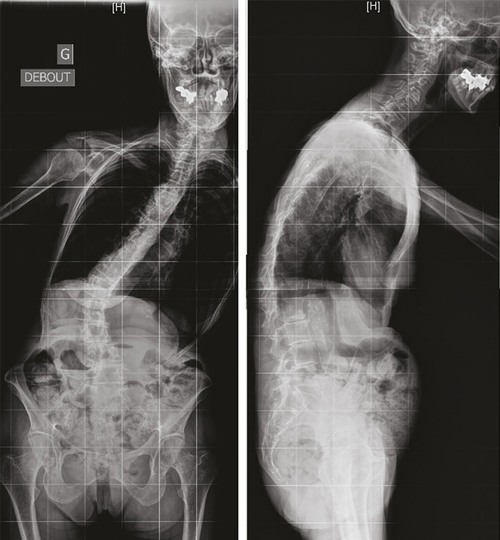

Le vieillissement du rachis commence tôt pour tous ses tissus constitutifs, il faut donc y penser dès 45-50 ans. Le vieillissement des structures ostéoarticulaires, musculaires et ligamentaires associé au vieillissement des autres structures, en particulier neurologiques, est responsable de différentes pathologies du rachis : scoliose dégénérative, cyphose lombaire dégénérative, canal lombaire étroit, ostéoporose fracturaire avec tassements vertébraux, spondylolisthésis dégénératif, camptocormie et tête tombante. Leur point commun : le retentissement sur la statique du rachis avec perte de l’équilibre du tronc (fig. 1 et 2).

Les conséquences de ces pathologies sont lourdes : douleurs, difficultés à la marche, préjudice esthétique lié à la déformation, parfois troubles digestifs et respiratoires (en cas de camptocormie notamment).